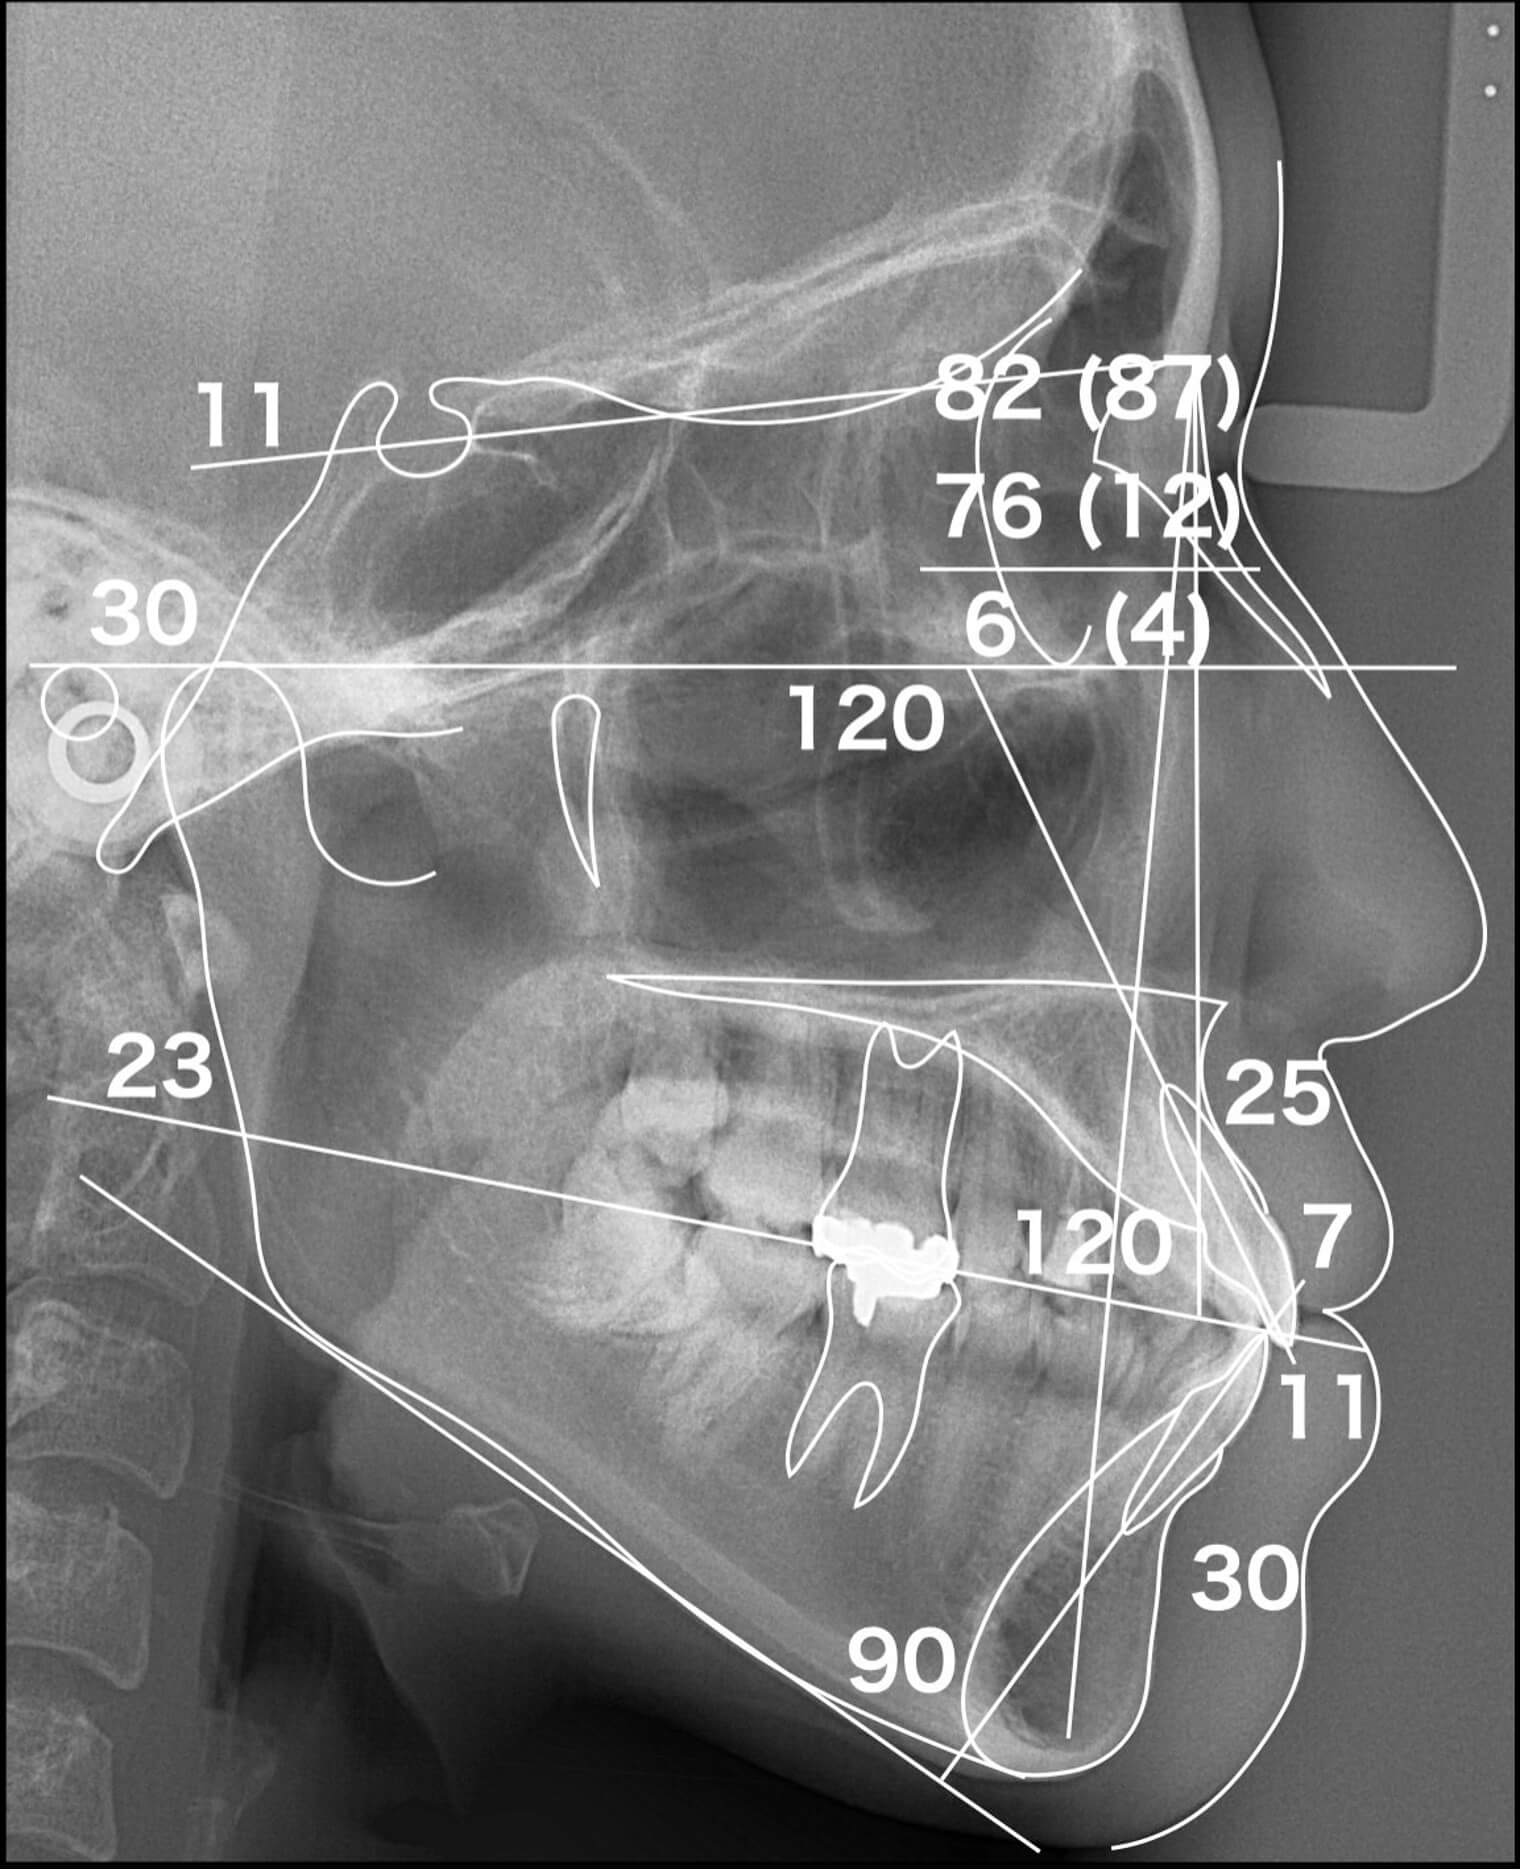

- セファロ(正面/側貌)

様々な検査を行い『1歯単位』ではなく『1口腔単位』として多角的に診断します。